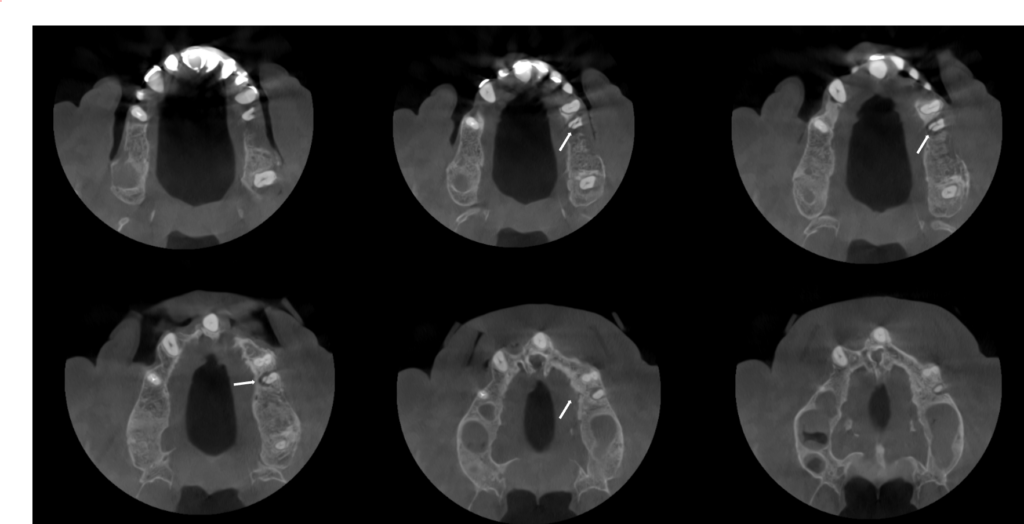

En la tomografía computarizada de haz cónico (CBCT) de ambos maxilares, evaluada mediante cortes axiales (Figura 2), transaxiales (Figura 3) y tangenciales (Figura 4), se observó una línea hipodensa de trayecto sinuoso que se extendía desde la superficie cervicovestibular hacia el tercio apical radicular palatino, comprometiendo el conducto radicular. Asimismo, se evidenció un proceso osteolítico perirradicular y pararradicular en el tercio medio radicular palatino, que ocasionaba adelgazamiento de la cortical de la tabla ósea.

CORTES AXIALES